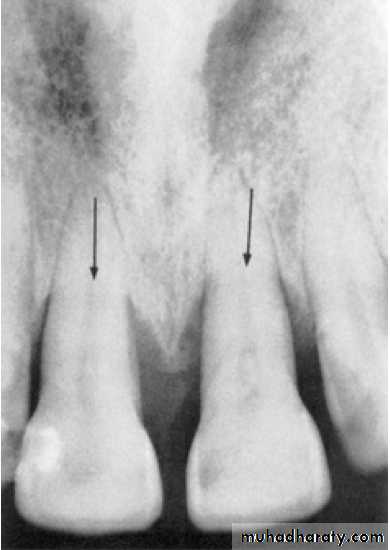

Radiographic Examination:

Radiographs are valuable for the diagnosis of periodontal disease,

estimation of severity, determination of prognosis, and evaluation

of treatment outcome.

The radiographic survey should consist of a minimum of 14

intraoral films and 4 posterior bitewing films.

Panoramic radiographs are a simple and convenient method of

obtaining a survey view of the dental arch and the surrounding

Structures.

The interdental bone normally is outlined by a thin, radiopaque line

adjacent to the periodontal ligament (PDL) and at the alveolar crest,referred to as the lamina dura.

Pattern of bone loss:

Several investigators have analyzed the distance from the CEJ tothe alveolar crest.

The height of interdental bone may be reduced, with the crest perpendicular to the long axis of the adjacent teeth (horizontal bone loss), or

angular or arcuate defects (angular, or vertical, bone loss)

could form.